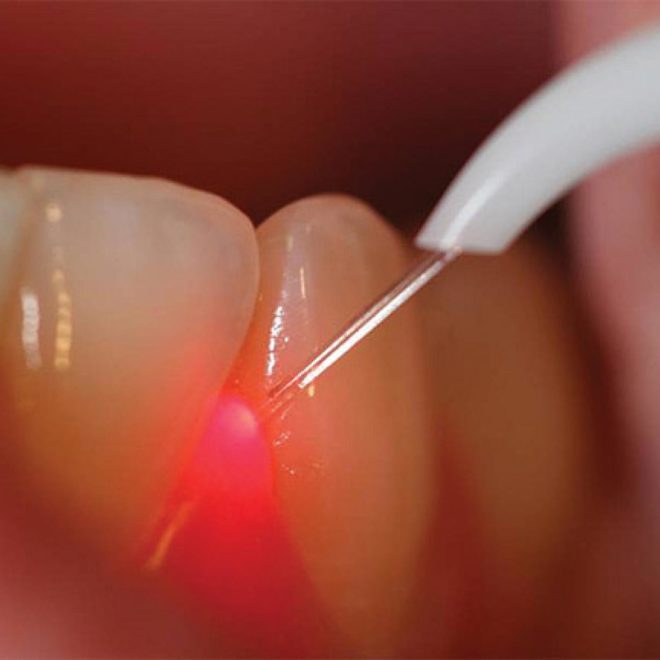

Laser: sono sicuri?

Sì, nelle mani di un dentista qualificato e addestrato. Anzi, in alcuni casi, confrontando il laser con gli strumenti odontoiatrici tradizionali, si osserva una riduzione o addirittura una minimizzazione del rischio di danno ai tessuti circostanti grazie alla sua precisione incomparabile, al controllo specifico delle potenze, alla durata dell’esposizione. La luce laser è molto più efficace rispetto alle fonti di luce convenzionali perché il laser produce un fascio intenso, stretto e concentrato di luce formata da una singola lunghezza d’onda; per contro, le fonti tradizionali di luce impiegate in odontoiatria, per esempio le lampade ad arco di plasma – forniscono un continuum di luce che comprende tutto lo spettro, anche le lunghezze d’onda infrarosse (calore) e ultraviolette. In altre parole, il laser è in grado di produrre esattamente la lunghezza d’onda richiesta per la specifica applicazione, consentendo di ottenere i risultati voluti con minor potenza e in un periodo più breve di tempo. E non solo: in confronto all’elettrocoagulazione e alle luci ad alta velocità, i laser garantiscono al paziente un ambiente molto più sicuro.

Laser: è vero che non si prova dolore?

Sì, è vero. Nella maggior parte delle applicazioni il dolore è completamente eliminato oppure, nel peggiore dei casi, significativamente ridotto grazie alla possibilità di un controllo preciso e selettivo. Il ricorso all’anestesia è quindi più raro. In moltissime procedure odontoiatriche, il laser minimizza la presenza di batteri pericolosi nella cavità orale, riduce o elimina il sanguinamento perché cauterizza mentre seziona, e riduce il dolore – tanto che sono innumerevoli le procedure che grazie al laser si effettuano senza la minima anestesia. Questo è dovuto anche alla velocità di pulsazione (frequenza), alla minima profondità di penetrazione, al minimo trasferimento di calore (lunghezze d’onda selezionate) ai tessuti circostanti. Oltre naturalmente a tempi di guarigione molto più brevi, a un minore gonfiore e a una minore infiammazione postoperatori, tutti fattori che contribuiscono a ridurre il fastidio associato con il processo di guarigione